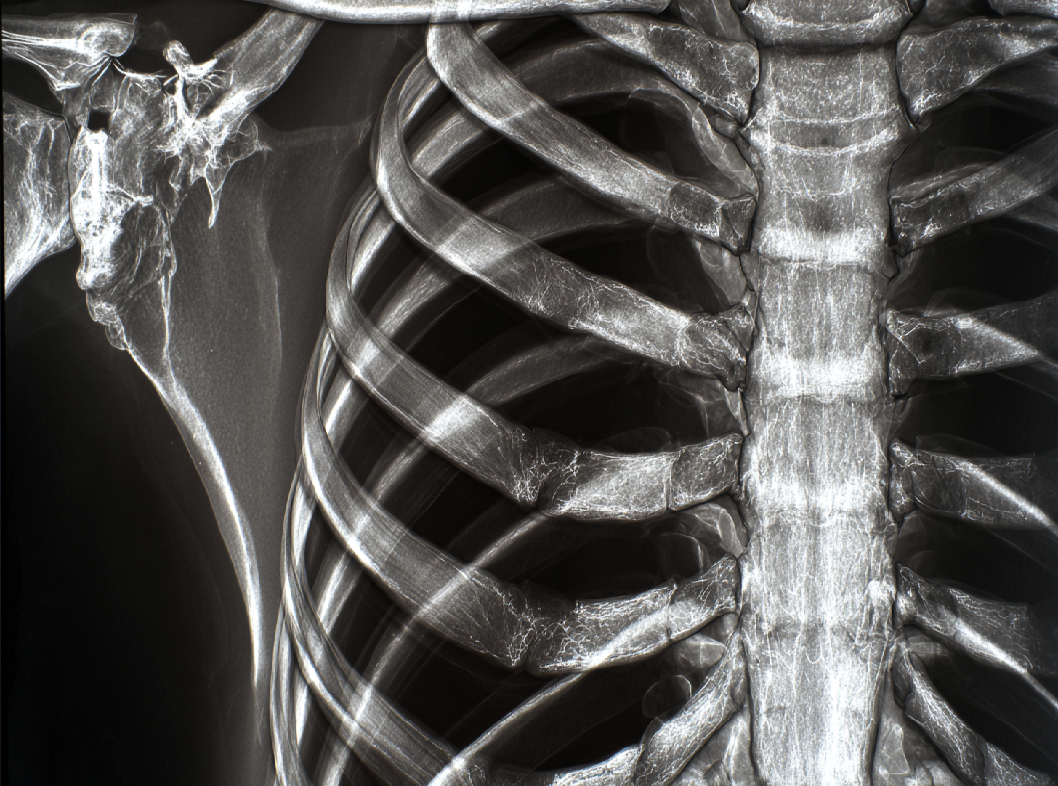

Клинические проявления ПР включают в себя боль в области повреждения, усиливающуюся при дыхании, кашле или движении тела. Часто можно наблюдать отек и синяк в месте перелома. Диагностика осуществляется при помощи клинического осмотра, рентгенографии и в некоторых случаях компьютерной томографии.

Перелом ребра (ПР) представляет собой повреждение структуры ребра, которое может возникнуть в результате травматического воздействия или сильного механического воздействия на грудную клетку. Рёбра являются костными элементами, образующими скелет грудной клетки, и их переломы могут иметь разнообразные характеристики в зависимости от механизма травмы.